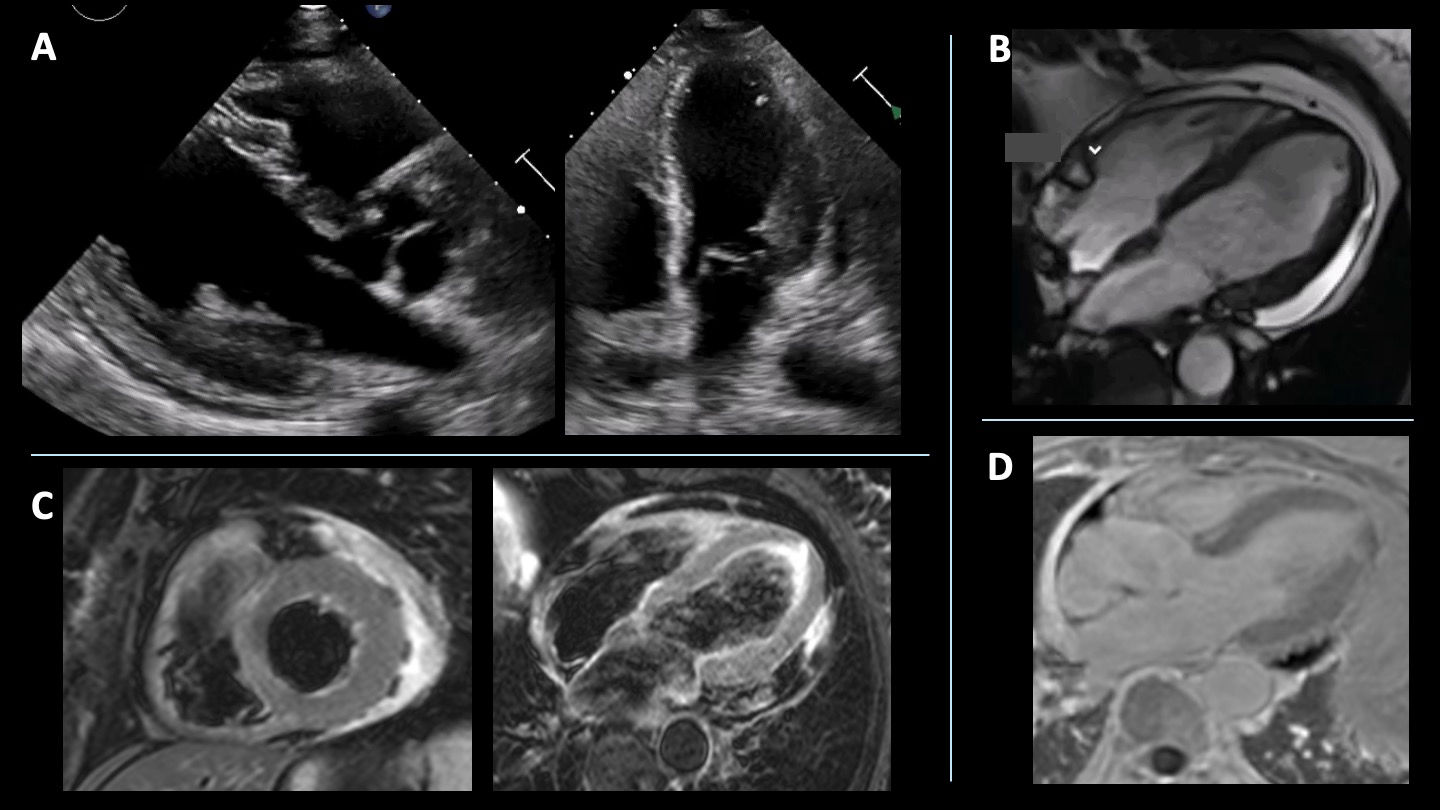

Electrocardiogram revealed sinus rhythm with a in lead III. Transthoracic echocardiogram (TTE) showed increased wall thickness in the mid-basal lateral and posterior segments of the left ventricle, preserved left ventricular ejection fraction, and small pericardial effusion (Figure 1A). Coronary computed tomography angiography (CT) ruled out obstructive coronary disease.

Initial etiological workup of increased left ventricular wall thickness. (A) Transthoracic echocardiogram at admission showed increased wall thickness in the mid and basal segments of the lateral and posterior walls of the left ventricle. (B) Contrast-enhanced chest computed tomography revealed an image suggestive of thrombus adherent to the anterior, lateral, and inferior walls of the left ventricle. (C) Contrast-enhanced transthoracic echocardiogram documented a left ventricular mass with reduced perfusion, suggestive of thrombus.

To investigate the increased left ventricular wall thickness, contrast-enhanced TTE was performed, revealing hypoperfusion in thickened segments, raising suspicion of thrombus, infiltration, or an inflammatory process with a thrombotic component (Figure 1C). Chest CT identified a hypodense mass within the left ventricle attached to the anterior, lateral, and inferior walls, suggestive of thrombus (Figure 1B).

Cardiac magnetic resonance (CMR) imaging confirmed mild left ventricular hypertrophy (12 mm) and severe segmental thickening (25 mm) in the basal lateral and posterior walls (Figure 2A). A large non-perfused intraventricular mass (31×17 mm), consistent with thrombus, was identified (Figure 2B). T2-weighted imaging showed myocardial oedema in the meso-basal posterior and lateral segments (Figure 2C), while late gadolinium enhancement (LGE) revealed a subendocardial pattern involving anterior, posterior, lateral, and inferior walls (Figure 2D), consistent with eosinophilic myocarditis associated with a large intraventricular thrombus.

Etiological investigation of MINOCA using cardiac magnetic resonance (CMR). (A) CMR in 4-chamber and 3-chamber views showed increased left ventricular wall thickness, more pronounced in the basal segment of the lateral and posterior walls. (B) Adherent mass suggestive of thrombus (29×16 mm) on early late gadolinium enhancement sequence. (C) T2-weighted sequence showing increased signal in the mid segments of the anterior, lateral and posterior walls. (D) Subendocardial late gadolinium enhancement in the mid-basal region of the posterior, lateral, anterior, and inferior walls and irregular not-enhanced mass adherent to the basal lateral wall suggestive of thrombus.